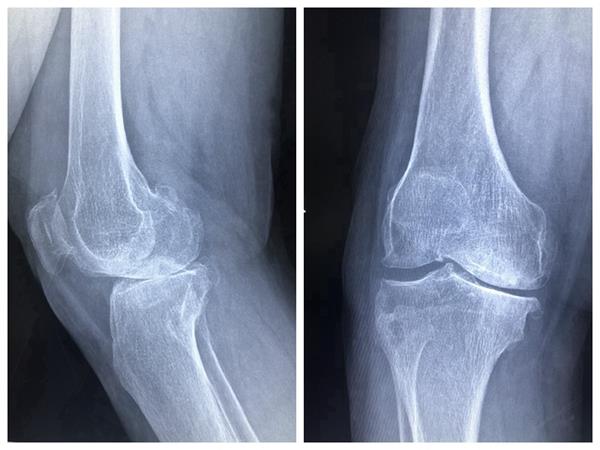

患者右膝關(guān)節(jié)術(shù)前、術(shù)后伸屈位放射影像

一位66歲的女性患者,右膝骨性關(guān)節(jié)炎終末期,經(jīng)過(guò)長(zhǎng)期保守治療無(wú)效,深受右膝病痛折磨,坐著輪椅由家人推著入住壽縣人民醫(yī)院骨科。科室主任劉本陽(yáng)組織醫(yī)師團(tuán)隊(duì)開(kāi)展討論,根據(jù)患者臨床表現(xiàn),結(jié)合多項(xiàng)檢查,確定人工膝關(guān)節(jié)置換為首選治療方法,并擇期手術(shù),為患者成功置換全膝人工膝關(guān)節(jié)。經(jīng)過(guò)精心治療護(hù)理,患者術(shù)后第四天下床活動(dòng),術(shù)后第七天出院回家康復(fù)休養(yǎng)。